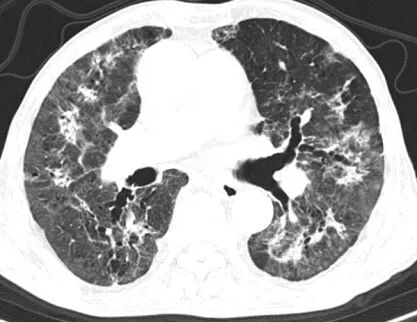

然而,病情的凶险程度远超预期,检查结果提示D-二聚体显著升高,CTPA提示右下肺动脉肺栓塞,肺部感染亦较前明显进展,病情进一步恶化。在呼吸与危重症医学科主任李芳芳带领下,团队迅速调整方案,加强抗凝与抗炎治疗。

胸部CT及CTPA

关键的tNGS检测结果揭晓了幕后真凶,耶氏肺孢子菌、巨细胞病毒、EB病毒及黑曲霉混合感染。至此,诊断完全明确,这是一例极为罕见的、在非HIV患者身上发生的PJP合并多种病原体感染,并叠加肺栓塞和呼吸衰竭的极危重病例。